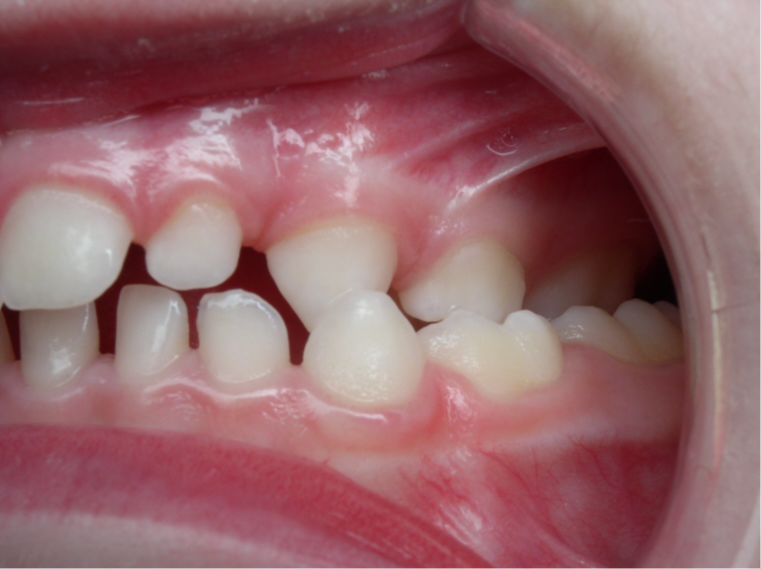

4.supraclusion inversé gauche 4 ans

inversion des dents postérieur coté gauche